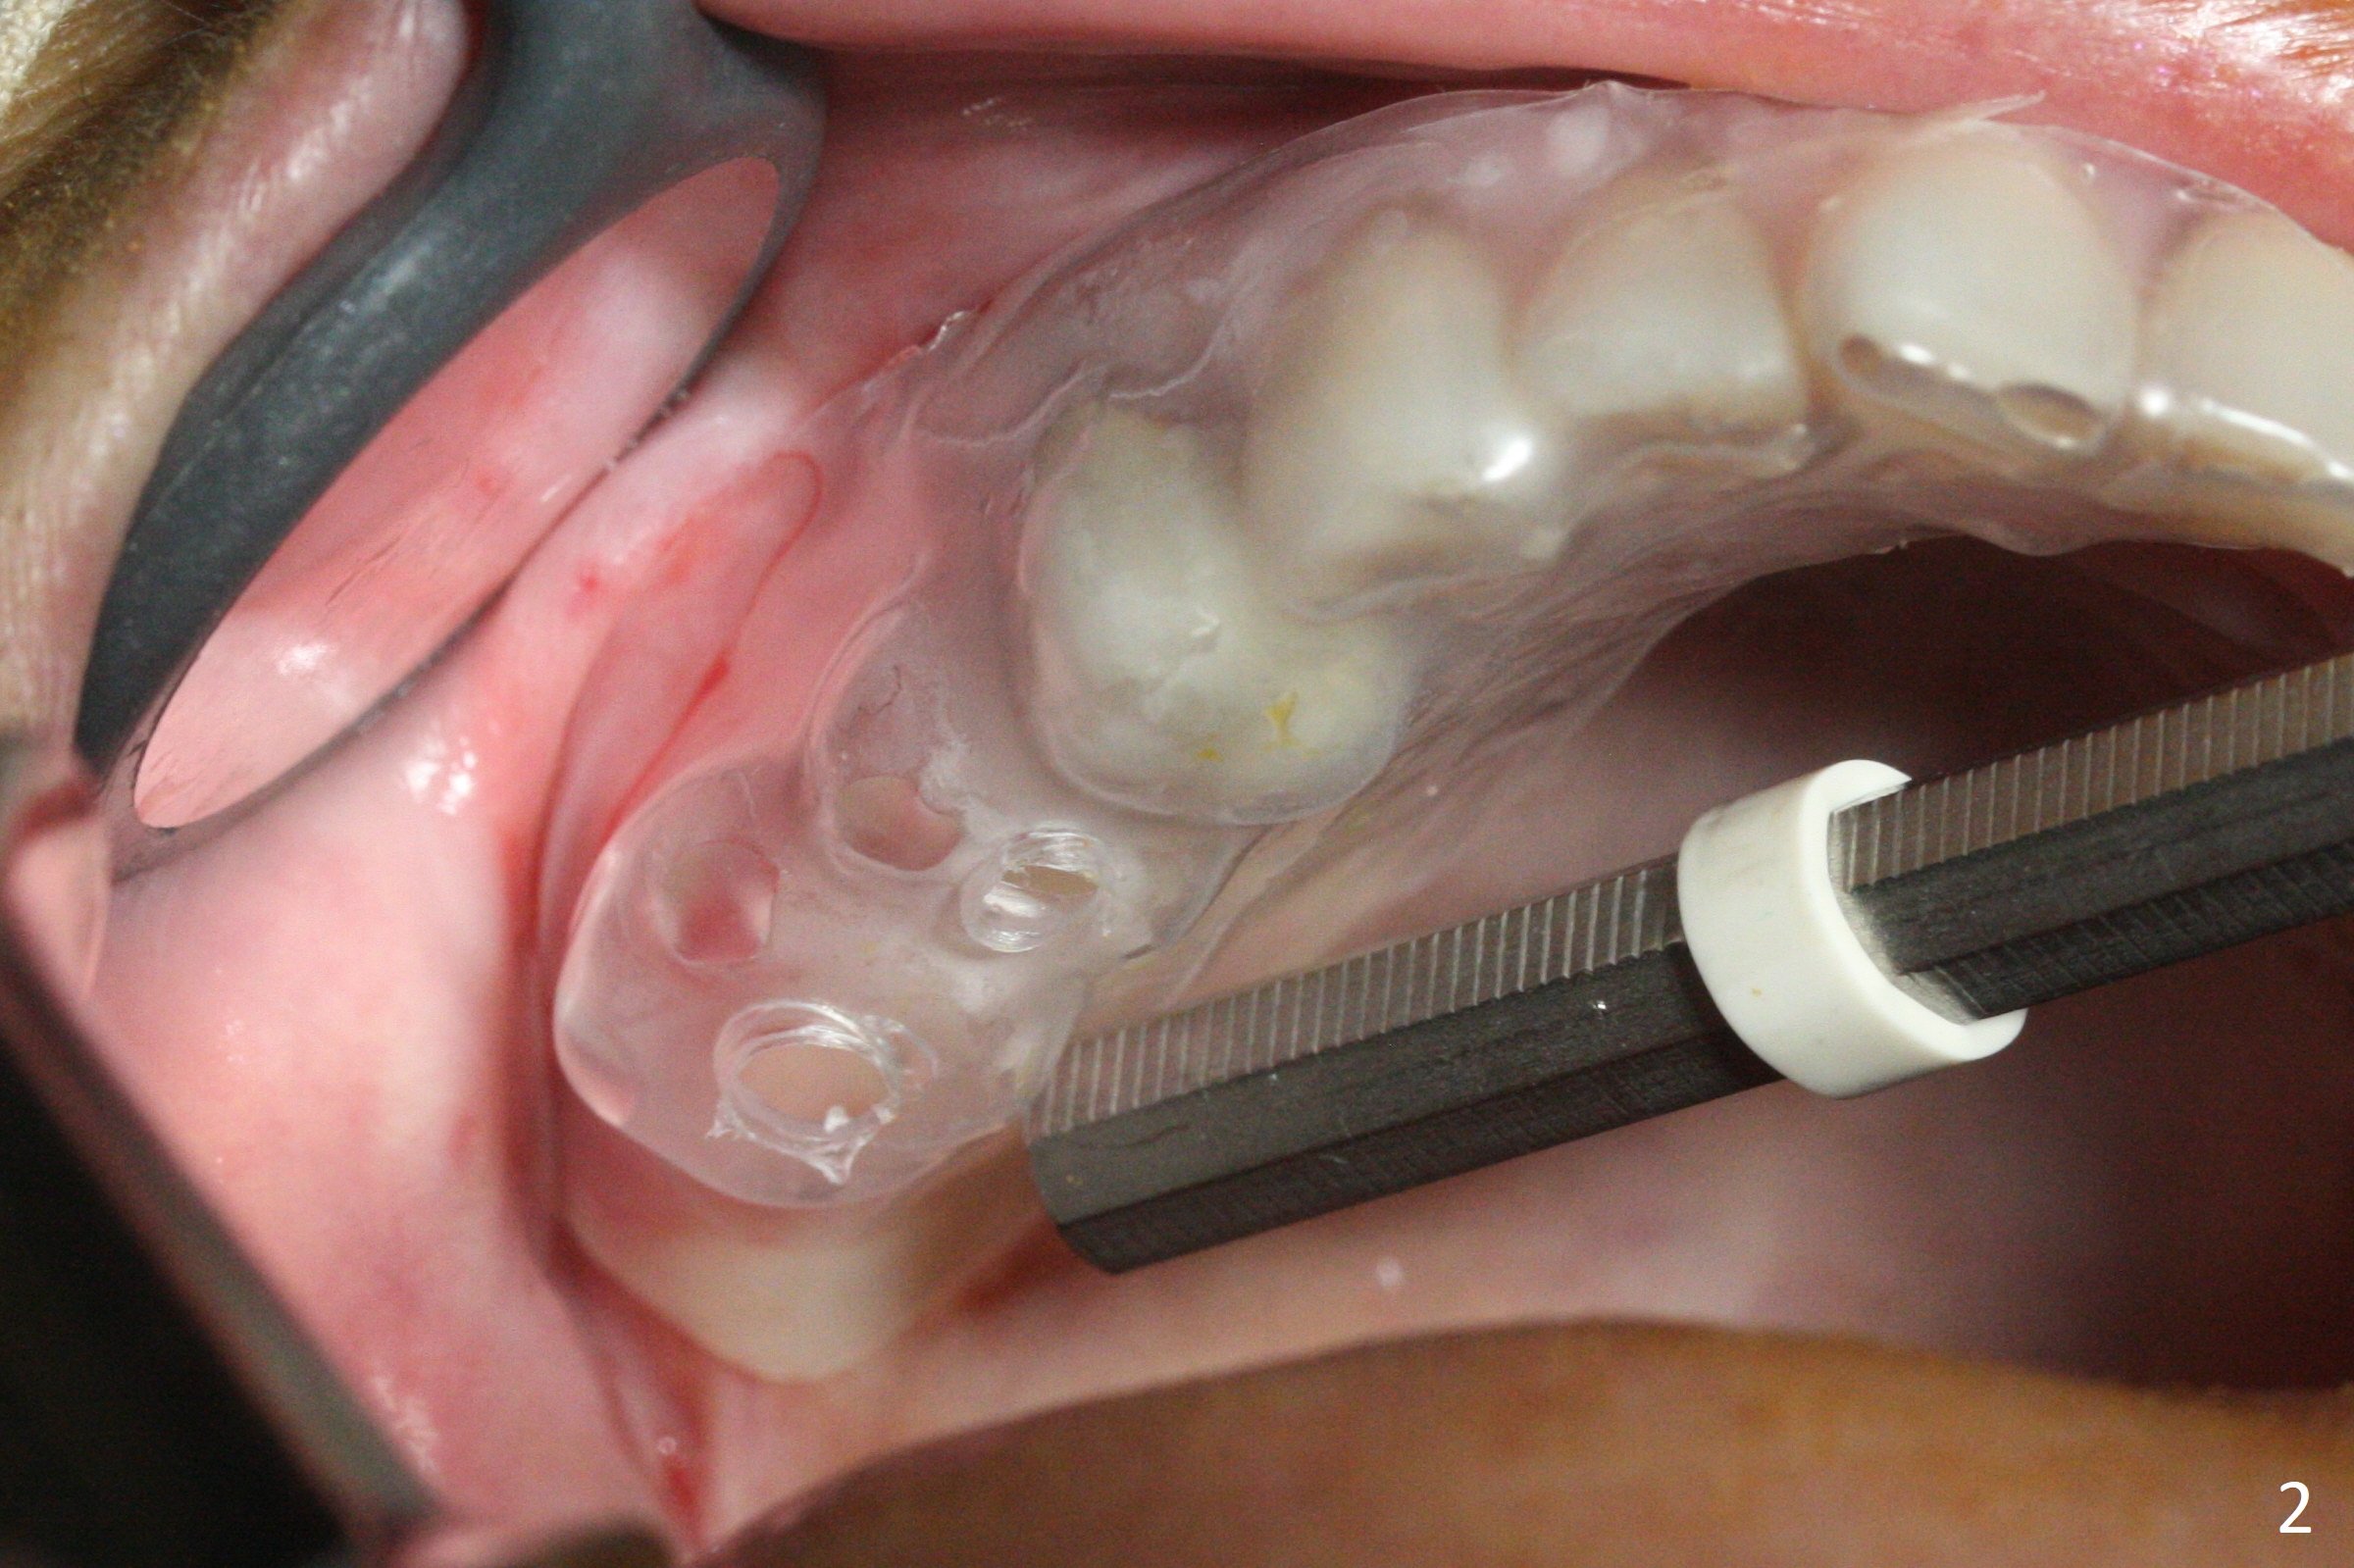

The ridge at #3,4 is wide (Fig.1). A surgical stent is placed (Fig.2) for initial osteotomy (Fig.3). When the stent is removed, the osteotomies need to move palatal (Fig.4 arrows). As two of 1.2 mm drills are in place (Fig.5), mesiodistal trajectories are found off (Fig.6). After the trajectories are corrected (Fig.7), the depth cannot be determined with PA (Fig.8, as compared to Pan (Fig.9)). Following 4.3 and 3.2 mm final drills at #3 and 4, 4.5x13 and 3.8x15 mm implants are placed with insertion torque of 35 and 50 Ncm, followed by 5.5x4(3) and 4.5x4(2) mm abutments (Fig.10). BWs show incomplete placement of the implant at #4 distal (Fig.11,12). Later the implant is placed ~ .5 mm deeper. Periodontal dressing is applied postop. CT-assisted surgical guide must be more efficient for this case with wide ridge. There is no bone loss around the implants 3 moths postop